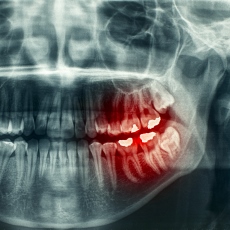

Your dentist will ask about your symptoms, look at your teeth, and probe them with dental instruments. In some cases, you may need dental x-rays.

- Panoramic Dental X-Ray (American College of Radiology; Radiological Society of North America) Also in Spanish

- Impacted tooth - a tooth that did not erupt (break through the gum) when it should have. It is usually wisdom teeth that are impacted, but it can sometimes happen to other teeth.

- Extractions (pulling teeth) for teeth that are impacted and causing problems or are too damaged to be fixed. You may also have a tooth or teeth pulled because of overcrowding in your mouth.